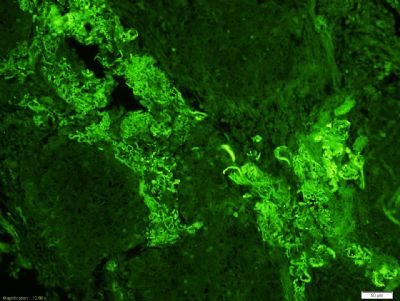

Fibrinogen beta chain,纤维蛋白原β链抗体产品应用WB=1:100-500 ELISA=1:500-1000 IHC-P=1:100-500 IHC-F=1:100-500 ICC=1:100-500 IF=1:100-500 (石蜡切片需做抗原修复)